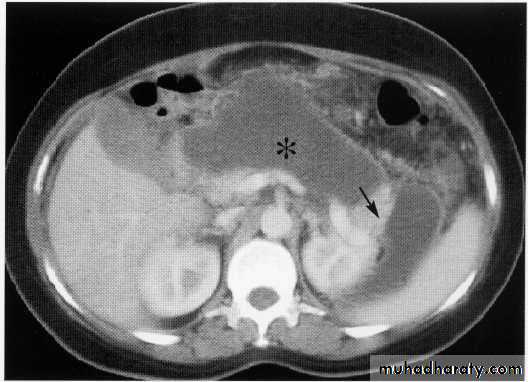

Gastric tumor with regional LAP

Gastric lymphoma

Exophytic tumor